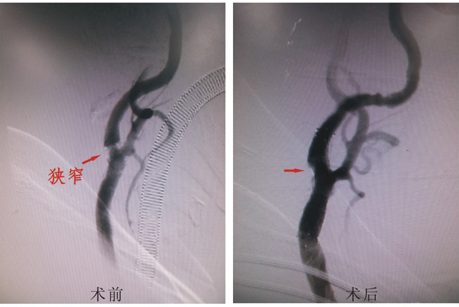

患者于2016年1月7日因“头痛、头晕1天”入院,急诊查头部CT示自发性蛛网膜下腔出血。入院后给予输液、控制血压、控制血管痉挛对症治疗,嘱患者避免剧烈咳嗽、用力排便等增加颅内压行为。查头颈CTA示左侧颈内动脉后交通段动脉瘤,左侧颈内动脉起始部狭窄40-50%。于2016年1月11日全麻下行“全脑血管造影”见:左侧颈总/颈内动脉重度狭窄,约80%,溃疡斑块形成,不规则;左侧颈内动脉后交通段动脉瘤,约5×5×3mm大小,形态不规则伴子瘤。介入下给予左侧颈总/颈内动脉重度狭窄行球囊扩张支架置入术;左侧颈内动脉后交通段不规则复杂动脉瘤采用最新双微导管技术给予彻底栓塞。术后患者恢复良好,四肢活动不受限,于2016年1月22日顺利出院。

本例为81岁高龄患者,左侧颈内动脉后交通段复杂动脉瘤伴同侧颈总/颈内动脉重度狭窄,如果全麻开颅手术夹闭存在极高风险并且不能一次同时治疗颅内动脉瘤及重度血管狭窄;而通过介入手术能一次治愈动脉瘤及血管狭窄,既预防了动脉瘤再次破裂出血又预防了血管进一步狭窄引起的大面积脑梗塞,提高了患者的生活质量。

一次性介入治愈高龄复杂动脉瘤伴血管狭窄,同时颅内复杂动脉瘤采用最新双微导管技术,体现了我们神经外科微创治疗学方向的重大进步。